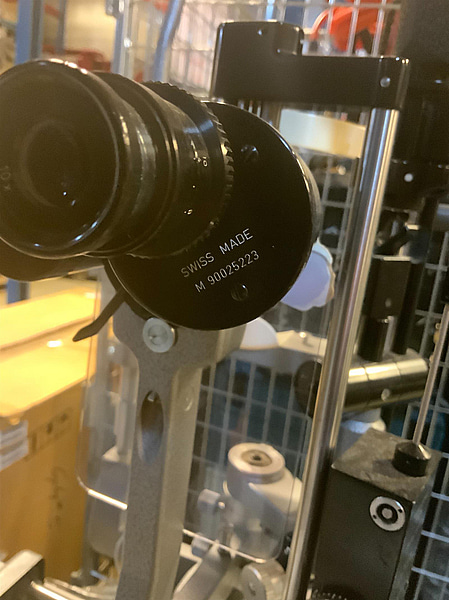

M90025223

Se bifogad dokumentation.Beskrivning på engelska, res. för felskrivning: